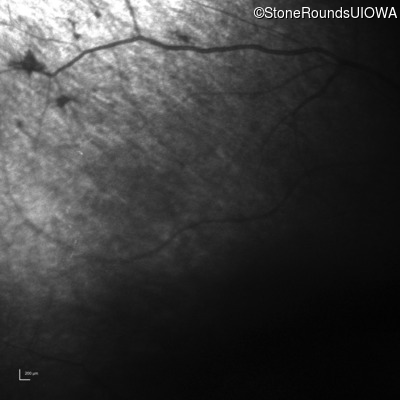

Infrared Fundus Photograph - Right - No Light Perception

Exemplar